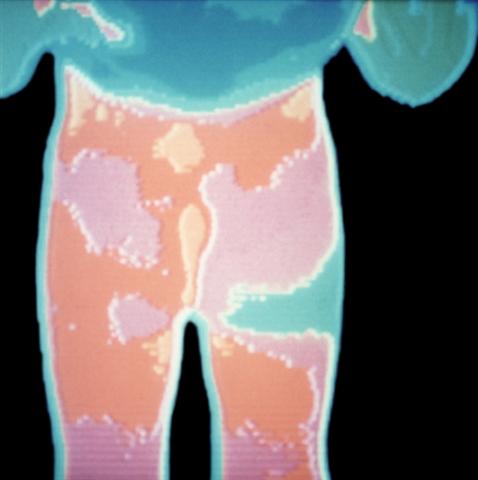

Рис. 15а). Термограмма ягодичной области при болезни Пертеса в начальной стадии (прямая проекция): увеличена теплопродукция области левого тазобедренного сустава.